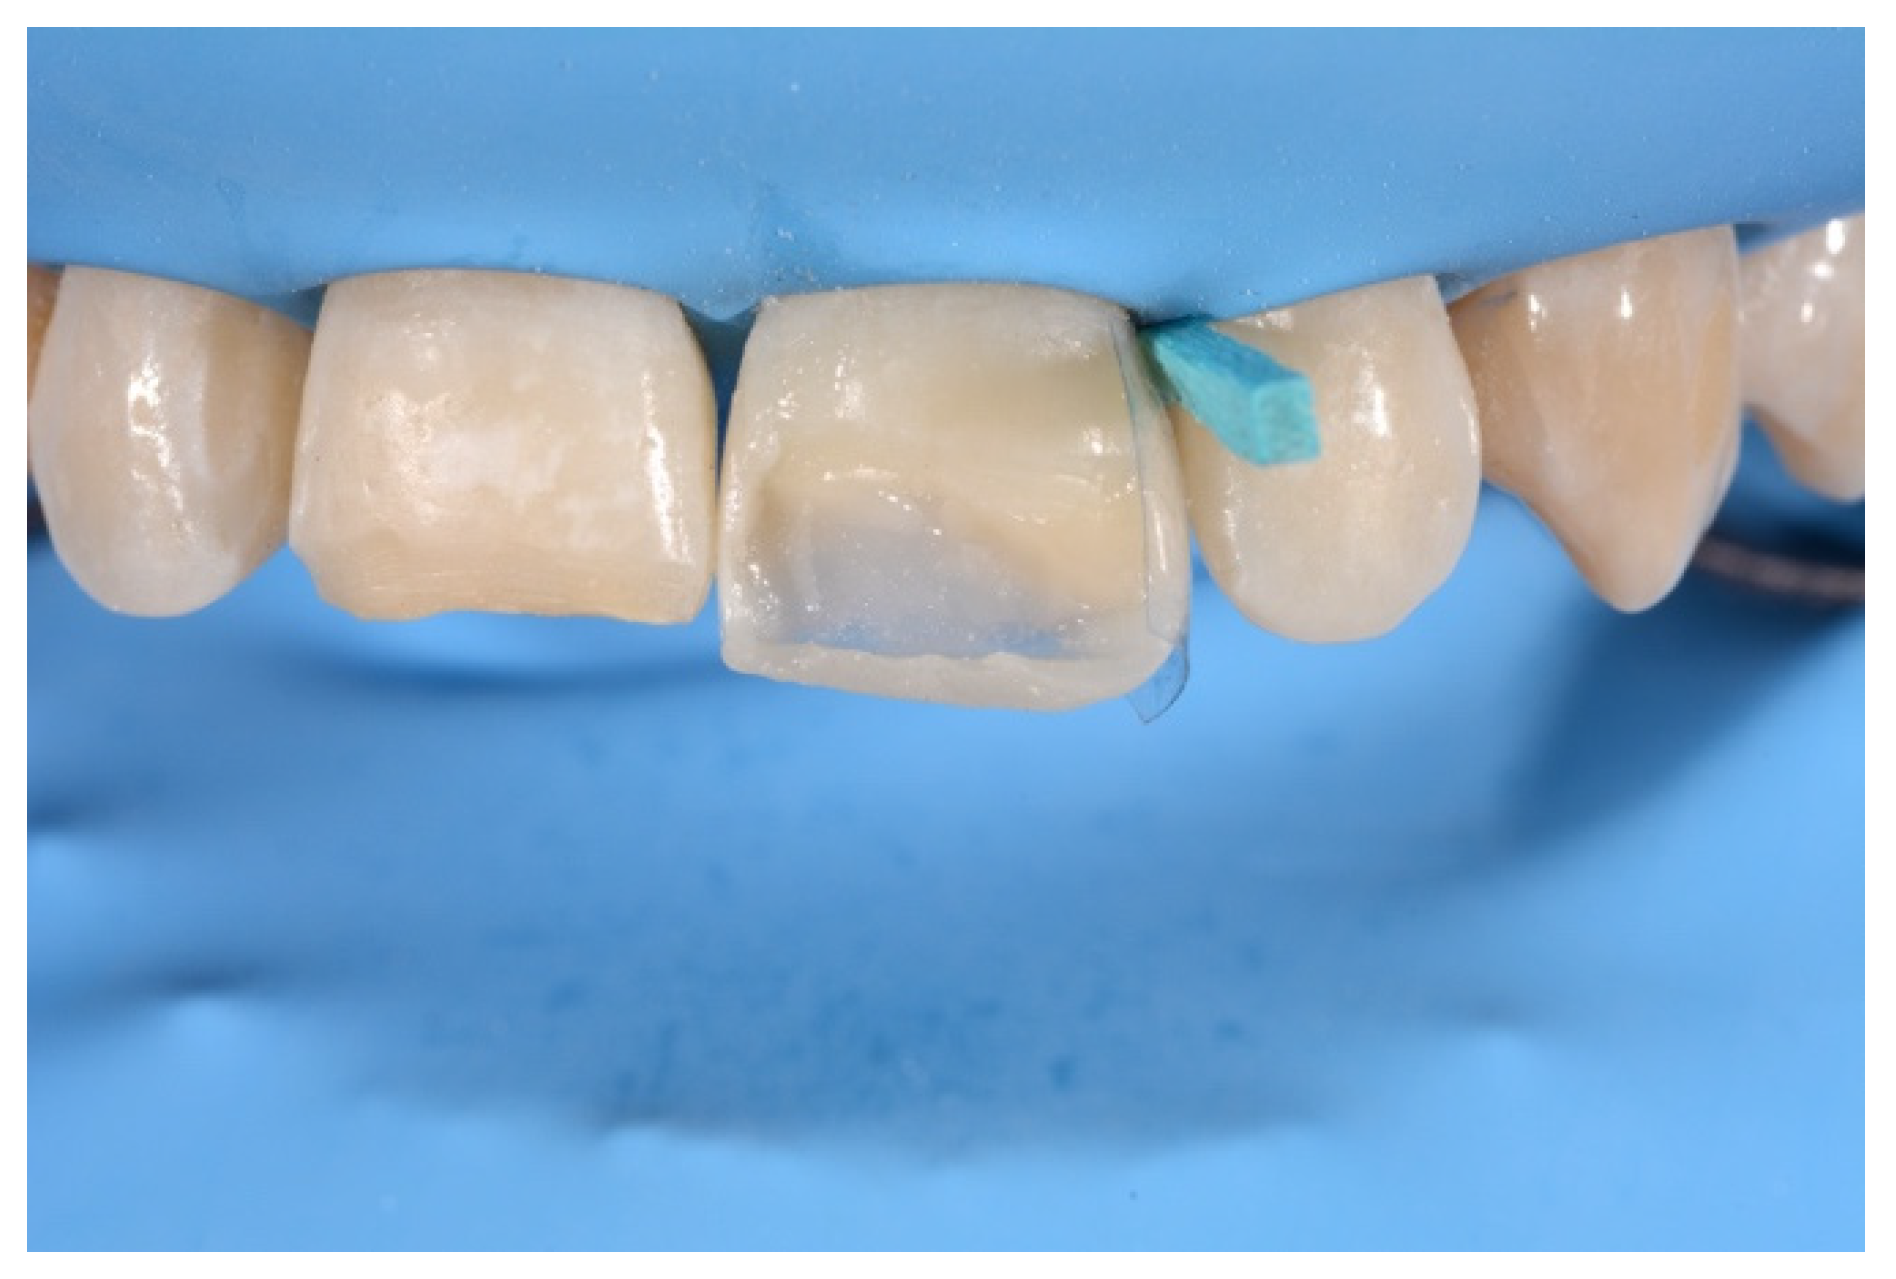

2. Case Presentation

- Molding palatal wall and incisal margin;

- Building interproximal walls with matrices;

- Layering free-hand buccal surface.